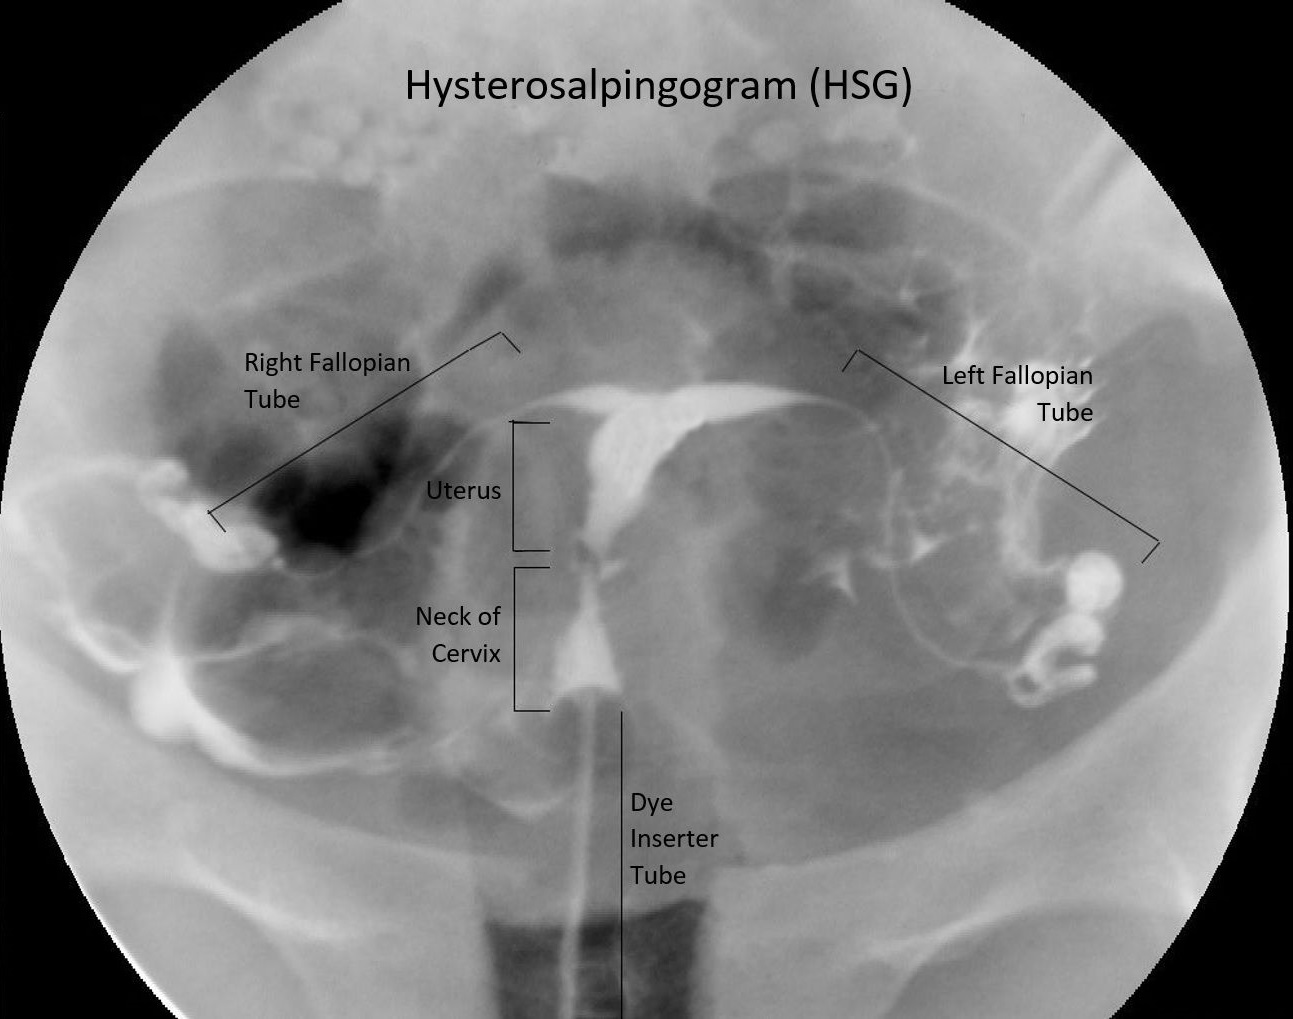

Histerosalpingografi (HSG) nedir?

Histerosalpingografi (HSG) fallop tüplerinin açık olup olmadığını ve uterin kavite şeklinin normal olup olmadığını belirlemek için yapılan bir x-ışını işlemidir. HSG işleminin yapılması yarım saatten daha az sürmektedir. Genellikle adet bitiminden sonra ve yumurtlamadan önce yapılmaktadır.

Hasta bir floroskop (gerçek zamanlı bir x-ışını görüntüleyicisi) altına ve sedyeye yatırılır. Jinekolog veya radyolog rahimi muayene eder ve vajinaya bir spekulum yerleştirir. Serviks temizlenir ve serviksin açılması için bir alet (kanül) yerleştirilir. Daha sonra hekim kanül yardımıyla rahimi iyodin (kontrast) ile doldurur. Kontrast tüplere girer ve eğer açıklarsa sonunda dökülür. Uterin kavite veya fallop tüplerindeki herhangi bir anormallik monitörde görülebilecektir. HSG’ da karın boşluğu ve yumurtalıklar değerlendirilemez veya endometriyozis teşhis edilemez. HSG’ dan sonra hastalar normal aktivitelerine hemen dönebilirler.